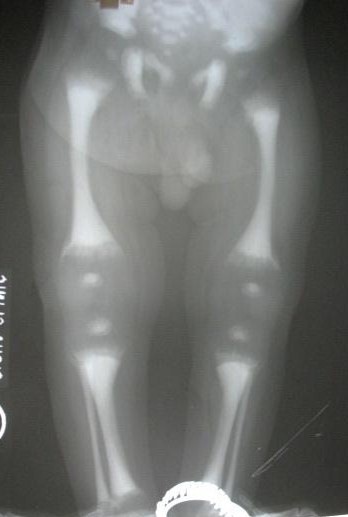

Infantile malignant osteopetrosis is a hereditary bone disease with intense positive balance of body calcium. Osteopetro-rickets is a very rare paradoxical association of infantile osteopetrosis and rickets. This is a case report of an infant with osteopetro- rickets. He presented with severe anaemia, splenomegaly, hepatomegaly and clinical signs of rickets. The clinical, biochemical and skeletal survey showed osteopetrosis and rickets. We also describe the pathophysiologic mechanism and various management options.